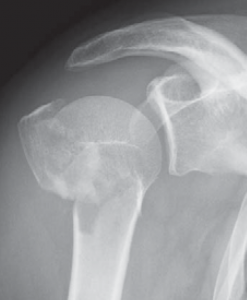

Oberarmkopfnekrose

Eine Sonderstellung nimmt die Oberarmkalottentrümmerfraktur ein. Werden bei dieser Fraktur mehr als 40% der Gelenkfläche zerstört, ist auch hier der Gelenkflächenersatz mittels Oberarmkopfprothese (Abb. 57) angezeigt.